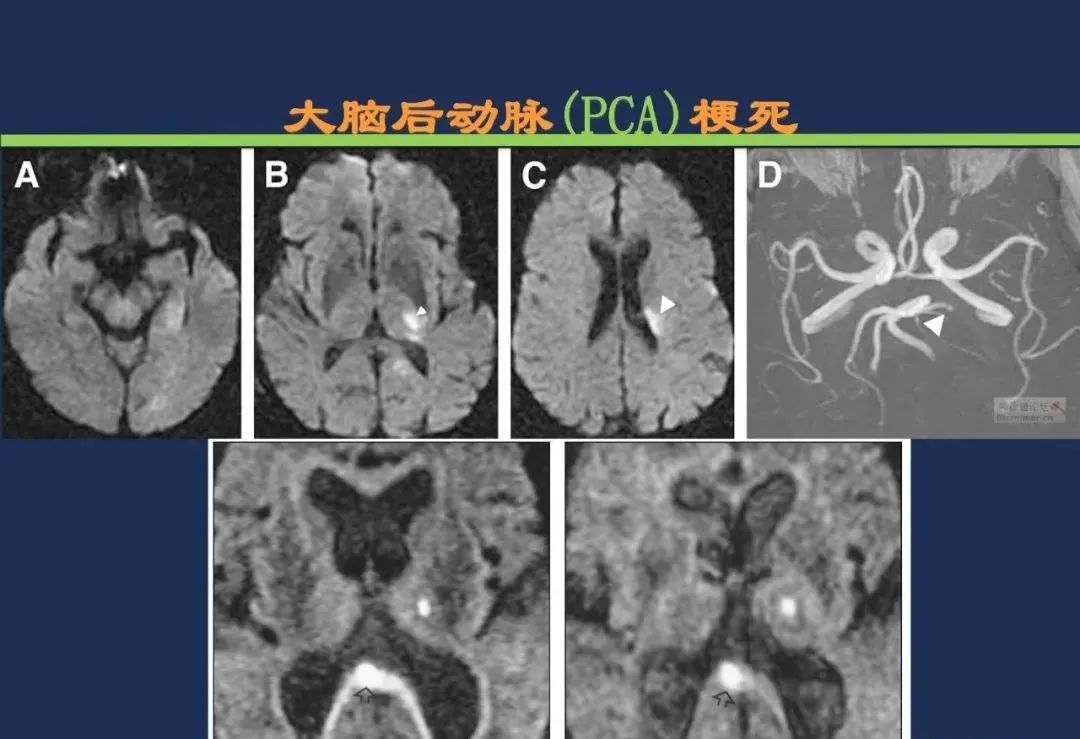

椎基底动脉梗死大脑后动脉丘脑穿通动脉-Percheron动脉